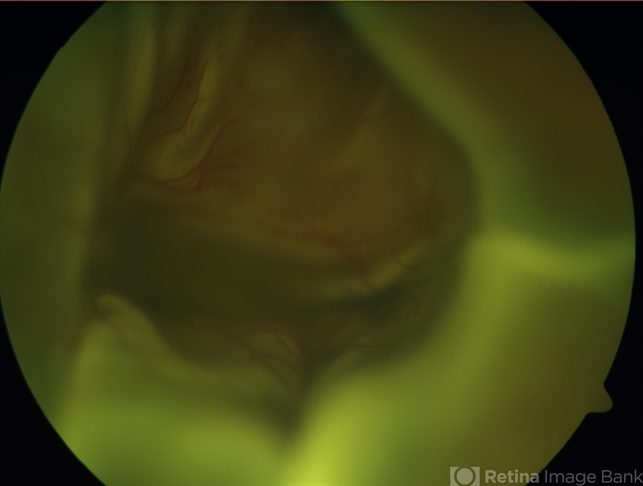

- A male patient 5-years-old presented to outdoor and found to have retinal detachment with choroidal detachment following blunt trauma